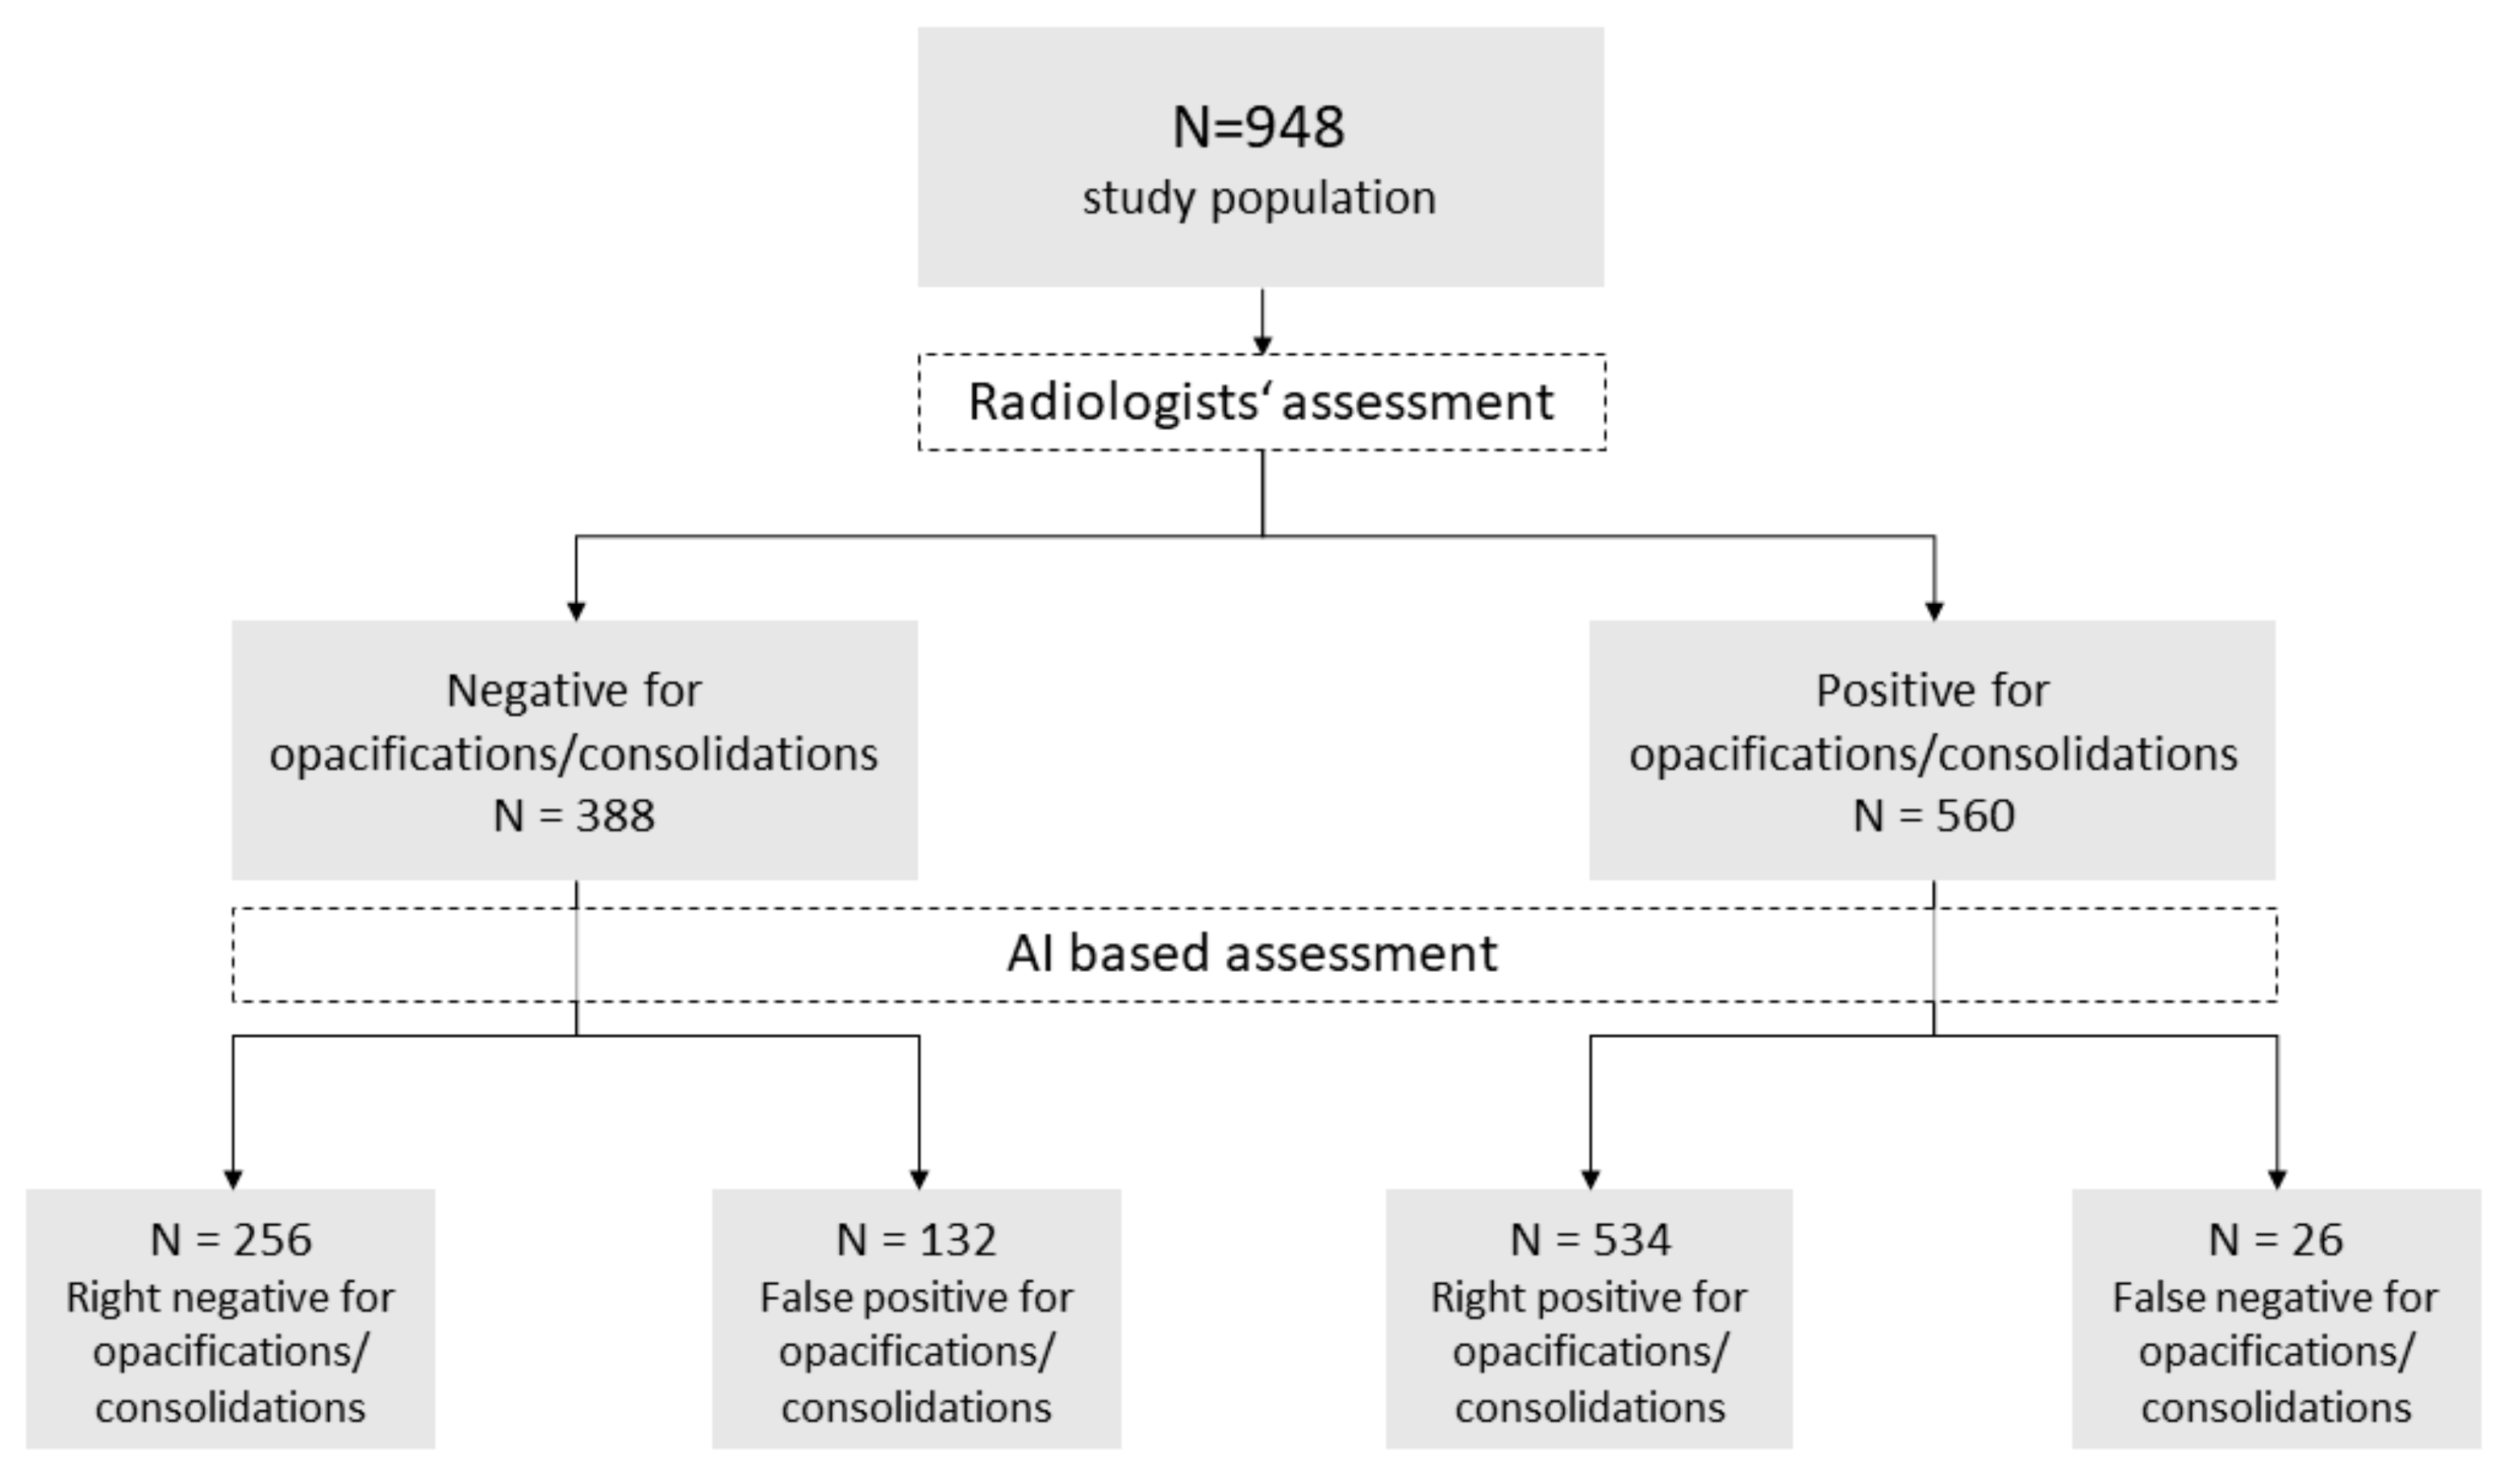

2.2. Imaging Evaluation

3.3. AI-Based Diagnostic Performance